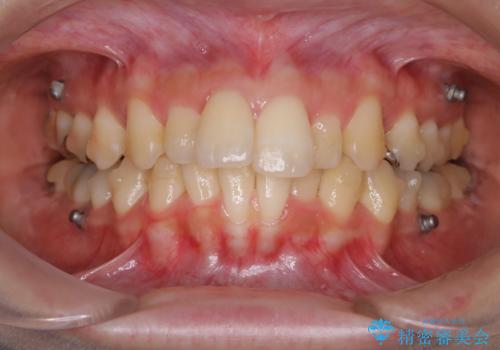

- インビザラインで矯正治療中にクリーニングを希望されました。PMTC60分コースで、クリーニングと歯ブラシ指導を行いました。

磨けているようでも、染出しをして目に見えるプラーク(歯垢)を確認することで、より正しいブラッシング方法を身につけることができます。インビザライン中は、歯にアタッチメントをつけるため、歯の表面がデコボコしてプラークが付きやすい状態になります。毎日のケアでしっかりと汚れを落として虫歯や歯周病・口臭のリスクを減らしていくことが大切です。定期的にメンテナンスを行い、ケアがどれくらい出来ているか確認したり歯科医院で専門的な機械や器具によるPMTCを行うことをおススメします。